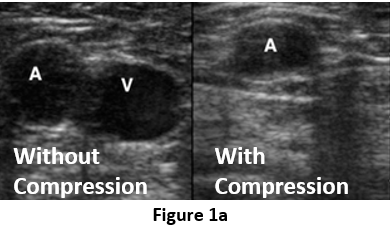

Teaching non-specialists to perform DVT ultrasound scans with real-time AI guidance.